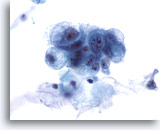

Grupos de células epiteliales bronquiales reactivas acompañan normalmente a las infecciones por aspergillus.

60x

Lavado bronquial

Grupos de células epiteliales bronquiales reactivas acompañan normalmente a las infecciones por aspergillus.

60x